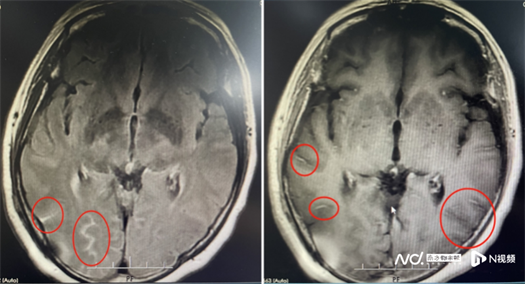

患者的影像资料。

尽管立即采用了抗真菌等对因治疗,但患者在住院期间还是出现了左眼视力下降,连光感都丧失了。复查腰椎穿刺发现脑脊液压力增高,提示颅高压。为避免长期高颅压导致头痛及颅神经损伤,匡祖颖安排患者转入神经外科行脑室腹腔分流术。